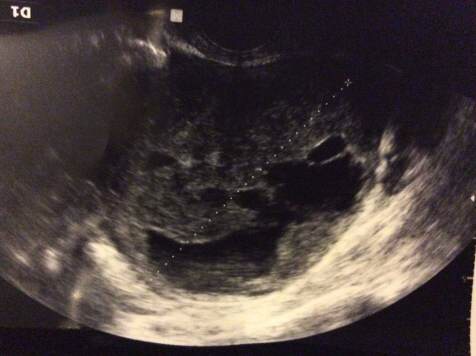

Alicjo - tez nie do końca wiem o co chodzi z tym jamistym... Chyba chodzi o to, ze ma jamy wypełnione krwią. Po operacji jeden lekarz nazwał go tez naczyniakiem. Pokażę Wam zdjęcie tego przystojniaka ;)

Załączniki

image.jpg

image.jpg (33.47 KiB) Przeglądane 6810 razy